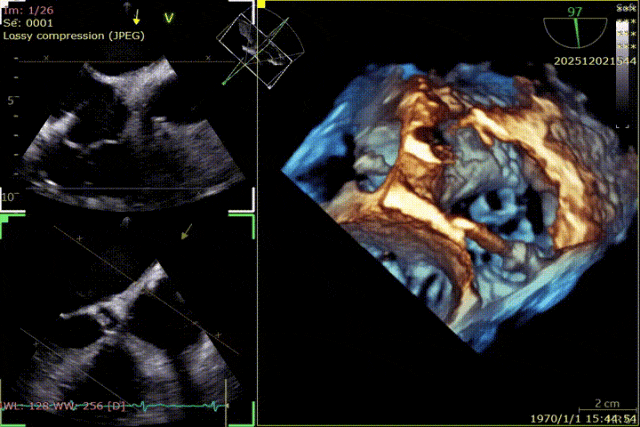

During the procedure, close collaboration was maintained with Dr. Yang Yan (anesthesiologist, Department of Anesthesiology) and Dr. Niu Ming (echocardiography specialist, team of Director Zhai Hong, Department of Cardiac Ultrasound). Guided by transesophageal echocardiography and assisted by DSA imaging, the tricuspid annular structure and regurgitation jet direction were precisely assessed. Ultimately, two 12T K-Clip® devices were successfully implanted. Immediate postoperative echocardiographic evaluation showed a significant reduction in tricuspid regurgitation from 4+ preoperatively to 1+, with a marked decrease in annular area. The surgical outcome was satisfactory.

Echocardiographic: Severe tricuspid regurgitation (grade 4+), with the regurgitant jet mainly located at the posteroseptal and central regions. No significant dilatation of the tricuspid annulus is observed. Mild myxomatous degeneration of the tricuspid leaflets is present, showing Barlow-like morphology, with leaflet prolapse of 3.7 mm in height.

Surgical Outcome

Preoperative Regurgitation: 4+

Annulus Area: 11.3 cm²

Postoperative Regurgitation: 1+

Annulus Area: 4.9 cm²